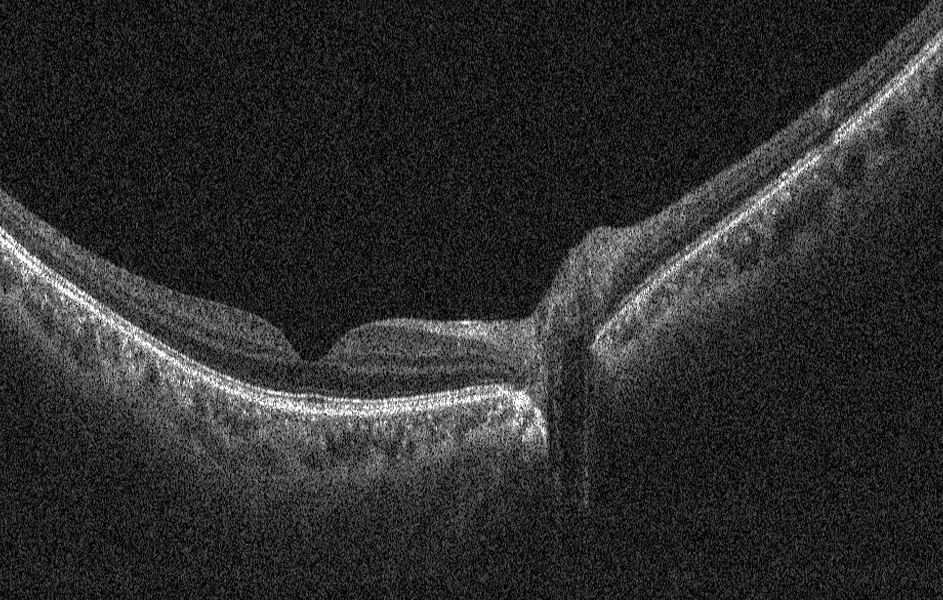

超强穿透效果

良好层析能力,更容易穿透眼底,

实现对脉络膜和巩膜组织信息的展示。

更大成像深度

灵活实现成像深度的改变,给眼前节成像、

大范围眼底成像、眼轴长成像提供便利与可行性。